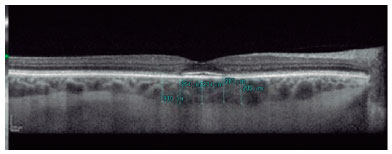

In the pre-macula stage, spectral domain optical coherence tomography (SD-OCT) can detect alterations in the photoreceptor layer, at the junction of the internal and external segments of the retina (ISOS), and in the retinal pigment epithelium (RPE). It is possible to identify discrete irregularities in the bilateral perifoveal region. In the initial phase of TR, small faults can be detected in the photoreceptor layers, ISOS, and RPE in the perifoveal region in addition to the above irregularities.

At the moderate maculopathy stage, loss of the physiological depression of the fovea occurs with interruptions of the RPE and ISOS in the parafoveal and perifoveal macular regions, characterizing the aspect in comet and macula in target. In the moderate and advanced stages, a typical fundoscopic TR lesion in the form of a bull’s eye can be identified, resulting from antimalarials. The advanced stage of maculopathy occurs with increased atrophy, foveal disruption, and visual acuity loss(15).

SD-OCT was useful for the classification of TR. Of the nine patients with TR caused by antimalarials, 44% (4) presented premacular maculopathy (Figure 1), 22% (2) at the initial stage (Figure 2), 22% (2) at the moderate stage (Figure 3), 11% (1) at the advanced stage (Figure 4), and none at the terminal stage (Table 3).